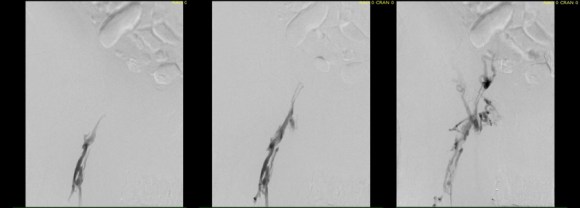

right initial venogram

Right injection from femoral sheath showing occluded iliac vein with collaterals

left initial venogram.png

Left injection